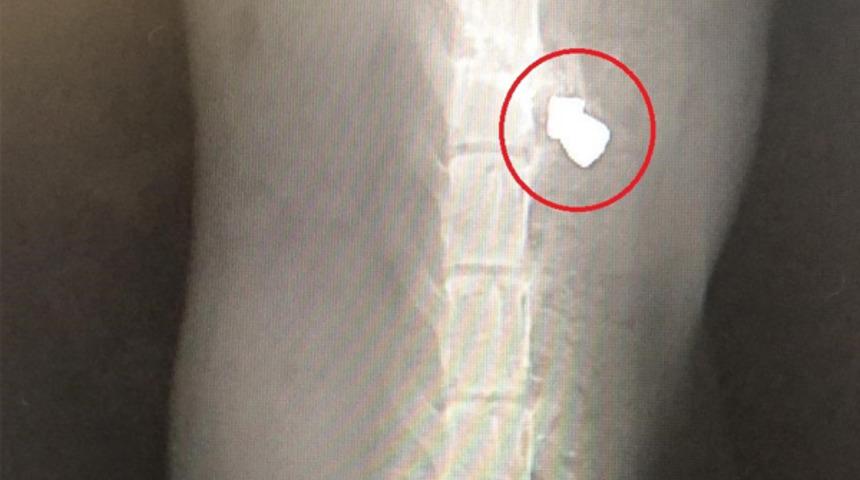

Hayvanseveler kediyle ilgilenip gece geç saatlerde olmasına rağmen Veteriner Ersin Arslan’a getirdi. Burada müdahale edilen ve tetkikleri yapılan hayvanın vücudunda saçma olması ve darp izlerinin olması herkesi şoke etti. Talihsiz kedi bulunmasının ardından 24 saat sonra hayatını kaybetti.

Kediyi bulan ve veterinere yetiştiren Bursa Hayvanlarla Yaşam Derneği Başkan Yardımcısı Şükrü Yaşar, "Orhangazi’deki dernek arkadaşlarımızı ziyarete gittik. Kırsaldaki ziyaretimizde kedi gözümüze çarptı. Yerde arka ayakları tutmaz vaziyette yatıyordu. Hemen aldık. Orhangazi’de imkanlar kısıtlı olduğu için gece 3 olmasına rağmen Bursa’daki Veteriner Ersin Arslan’a getirdik. Burada yapılan tetkikler sonucu şoke olduk. İlk önce saçma atıldığını ardından sert bir cisimle vurulduğunu öğrendik. Bütün imkanlar seferber edildi, ama kurtulamadı. Çok acı bir durum, üzgünüz" dedi.